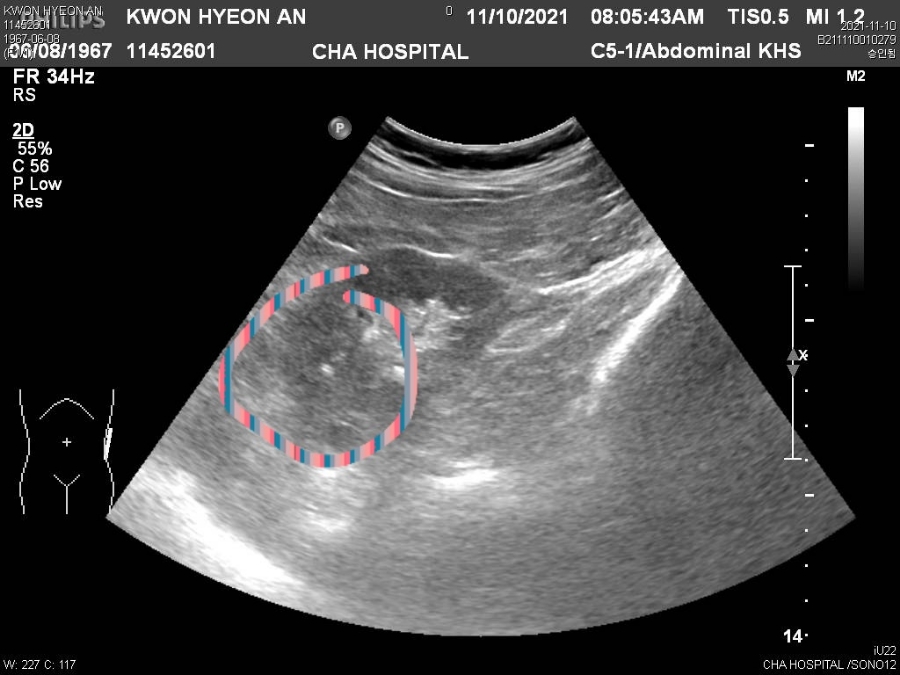

하얀 점이 1~2mm 정도 담석이에요건강검진을 10년 전부터 계속 받아왔고 쓸개에 석이 1~2mm 정도 있다는 결과를 받아 미루었으나

차병원에서 찍은 CT, 초음파, 대장, 위카메라 CD를 보여드리며 담석증 소견과 신장 10cm 정도의 물집을 제거하도록 원장.

성모병원 외과전문의가 있는 바로 초음파실로 찾아가 진료 시작 후 10분 정도 초음파로 구석구석

구석구석을 살펴보고 진료실로 오라고 해서 진료실에 가서 결과를 듣기 시작했어요.

말하면서 담석염입니다담석증으로 사용하는 게에 있는 돌이 몇 번이나 빠져 나오기 때문에 담낭벽에 염증을 일으키는 병입니다.